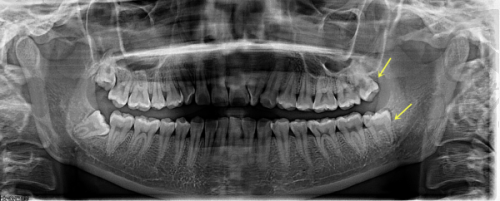

主力设备包括:CBCT口腔锥形束CT(三维成像,把你的牙和骨头360度观察)、iTero口扫仪(做牙齿矫正时完全不用咬那口印模糊糊膏体)、德国卡瓦牙科治疗仪、CAD/CAM修复系统(数字化制作牙冠)……这些设备,就连特别多二级医院都不一定齐全。

设备不光“有”,还“会用”,不少患者表示医生会现场展示自己的牙骨图像、咬合关系模拟图,甚至可以提前做“数字种植”预演种几颗牙、角度是多少,全给你算清楚,这种体验感直接拉满。